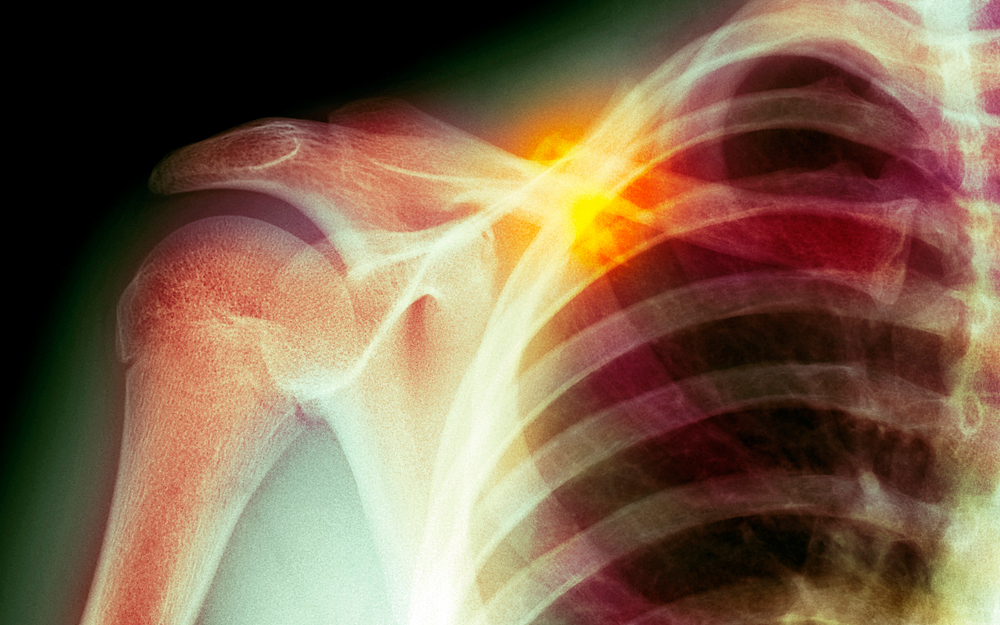

Work being done at Cedars-Sinai may revolutionize how severe orthopaedic injuries are treated. By harnessing the power of resident stem cells, gene therapy and ultrasound, researchers are testing the possibility of helping the body grow new bone after complex or catastrophic damage. The method could be life-altering for patients with such injuries.

"We're looking at bones with complex fractures, or that have been shattered and can't be repaired in conventional ways," says Zulma Gazit, associate professor of Surgery and co-director of the Skeletal Regeneration and Stem Cell Therapy Program at Cedars-Sinai. "That type of damage can be caused by violent accidents, and for military personnel it can happen on the battlefield. Right now, patients with the most serious orthopaedic injuries don't have a lot of options and really suffer," she adds. "Sometimes the limb needs to be amputated because the fracture won't heal and the prostheses or plates will not last in the long term. We want to prevent that."